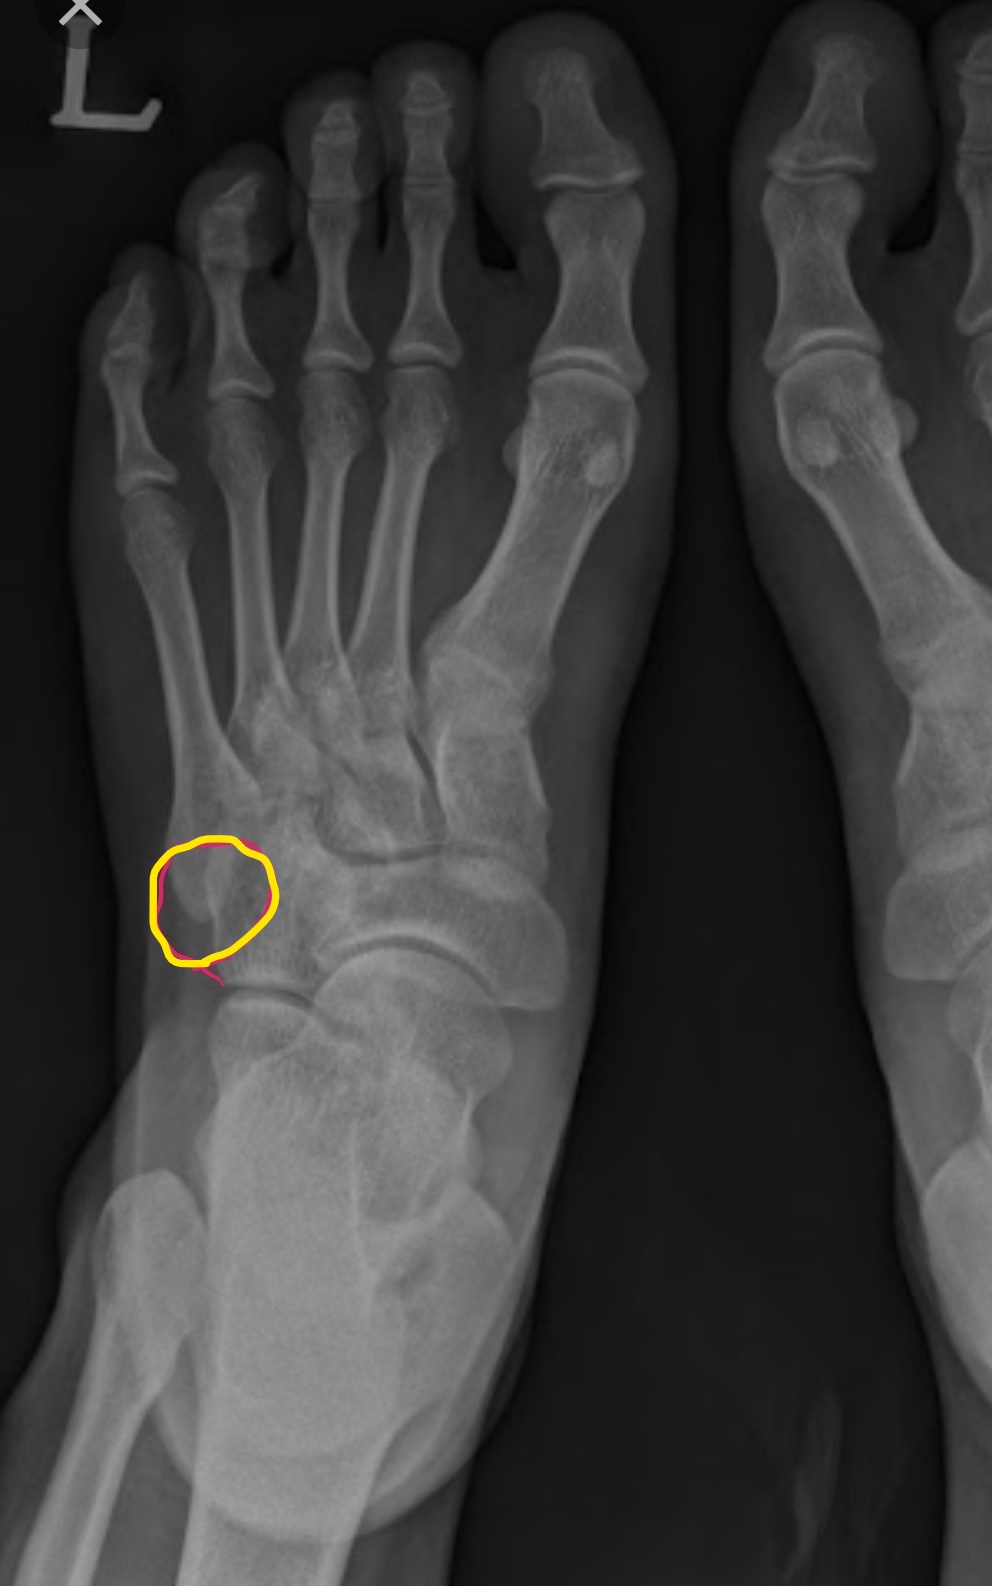

X-ray를 촬영하고 골절은 아닌 것 같은데 통증이나 붓기가 이상하다고 했다.

그리고 초음파를 찍어 보자고 했고 초음파에서 골절로 의심되는 부위를 발견하여

X-ray로 자세를 달리하여 촬영했다.

새끼발가락과 발등 연결 부위의 골절. 뼈끼리 연결되는 부분이라 뼈가 붙을 때까지 4~6주간 통 깁스를 해야 한단다.